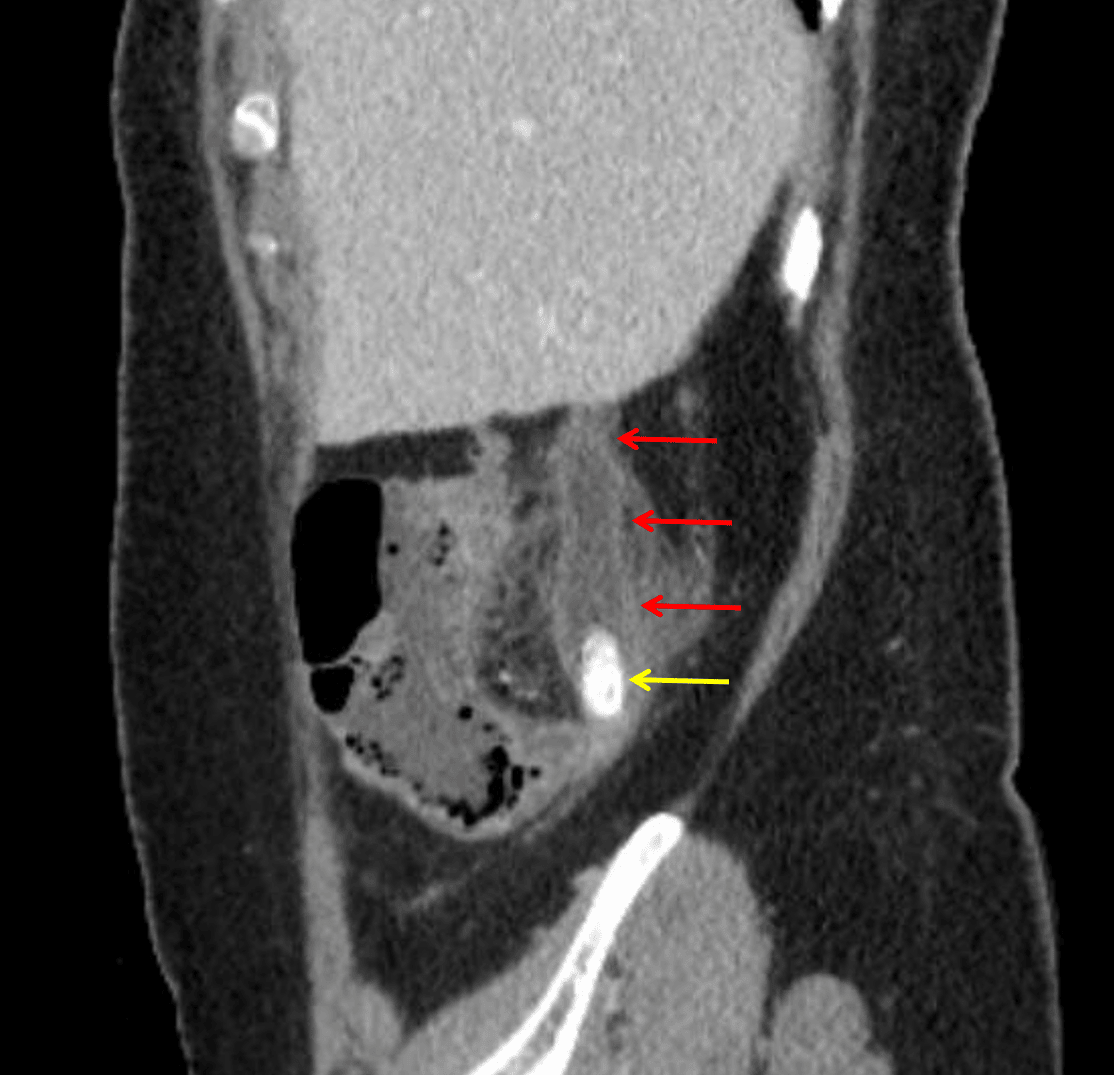

Acute appendicitis: dilated appendix with wall thickening and hyperenhancement (red arrows) and appendicoliths in the base of the appendix (yellow arrow).

• Dilated retrocecal appendix measuring up to 19 mm in diameter with diffuse wall thickening and multiple appendicoliths measuring up to 12 mm in the base

• No areas of mural hypoenhancement or discontinuity

• Periappendiceal fat stranding without fluid collection or free air